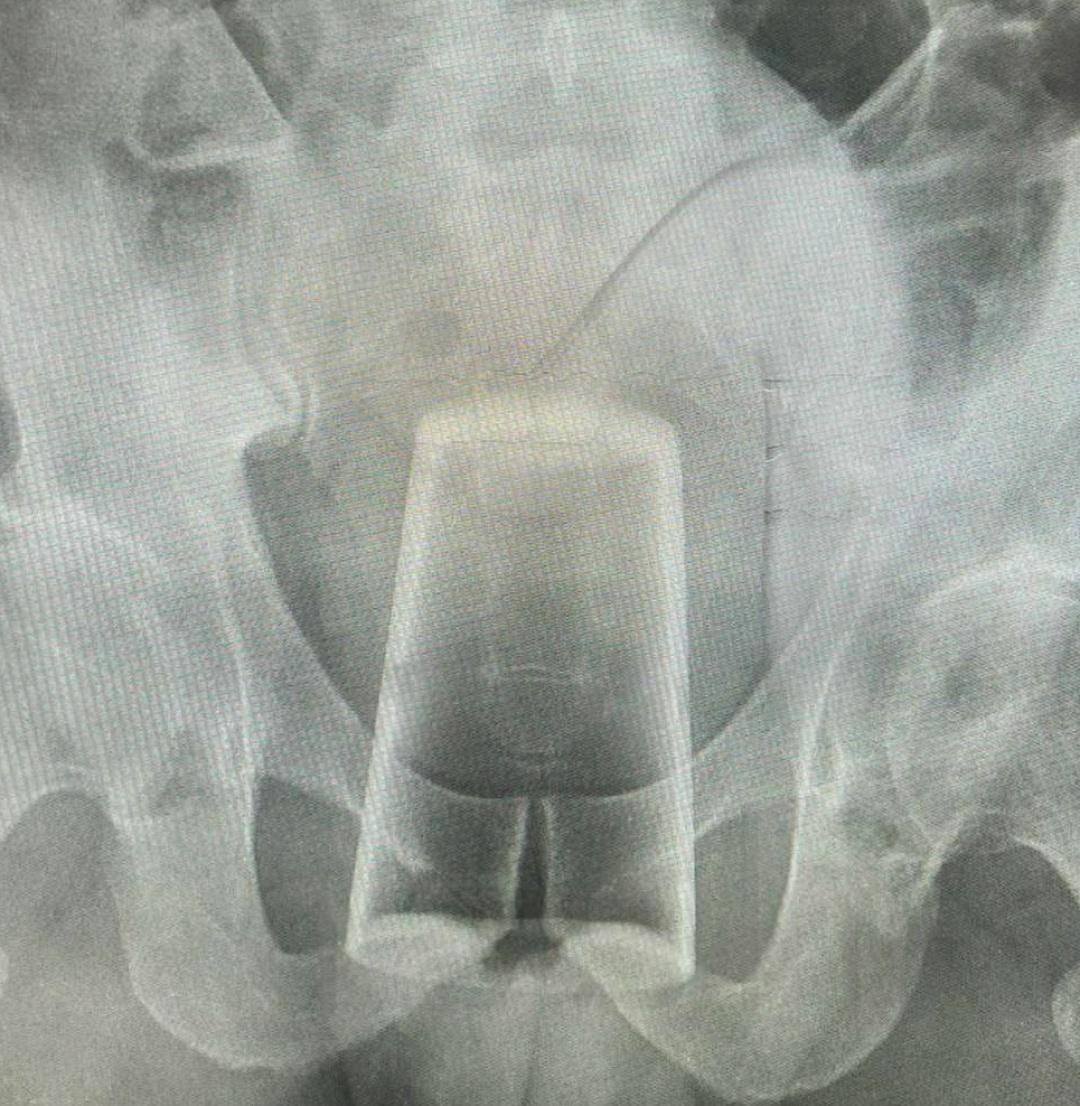

Уфимец сел жопой на стакан во время празднования 23 февраля и попал в больничку.

Уфимец сел жопой на стакан во время празднования 23 февраля и попал в больничку.

Любитель ...ьных утех выпивал с другом, а потом, по его версии, «поскользнулся и упал» — стеклянный стакан оказался в прямо в заднице. Самостоятельно вытащить его не получилось, пришлось вызывать скорую.

Врачи извлекли посудину, посоветовали больше не проводить такие конкурсы и наблюдаться у специалистов.